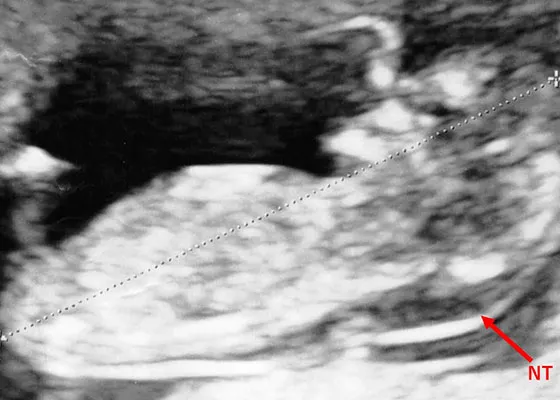

20代18トリソミー|健診で先生がNT肥厚と書いたのに説明してくれない

NIPTの後に赤ちゃんのNT肥厚(首の後ろのむくみ)が指摘